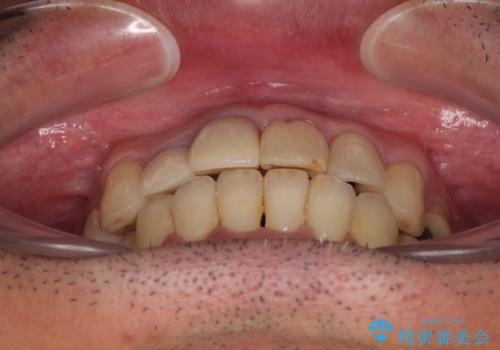

隠れている前歯 インビザライン矯正治療と前歯のセラミック治療

- 隠れるほどに内側に転位しいてる前歯を気にして来院された患者様です。

内側に転位していた前歯は、矯正治療では治しきることができませんでしたが、幸いにもオールセラミッククラウンに置き換える予定であったため、希望通りの仕上がりとなりました。